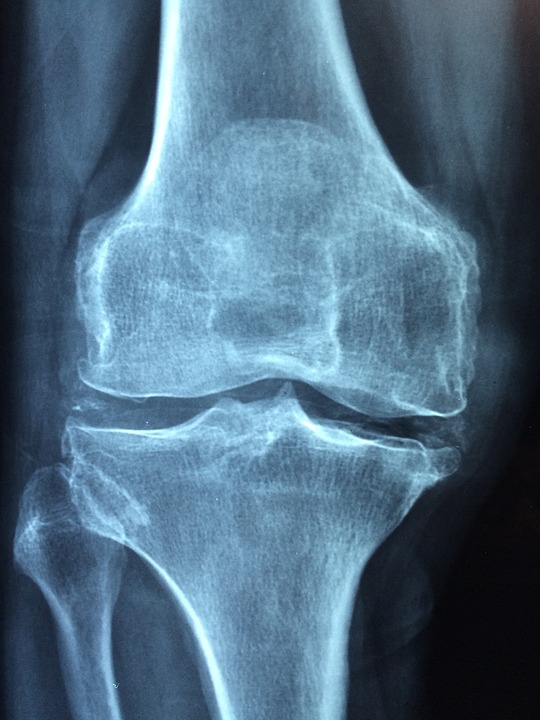

Tra le patologie che possono causare dolore cronico c’è la poliartrosi, un’infiammazione cronica delle articolazioni.  Nel caso di poliartrosi cronica, il processo infiammatorio causa il progressivo danneggiamento delle articolazioni.    Tra i sintomi più comuni riscontrati ci sono sicuramente il dolore e la difficoltà di movimento della zona interessata.

Questo processo infiammatorio può essere distinto in acuto o cronico e verificarsi a carico di più articolazioni nel corpo. Le articolazioni quando vengono colpite da questa patologia si presentano calde, arrossate, gonfie, il processo degenera nella fase più critica e dolente che è quella delle lesioni a carico delle articolazioni stesse.

Il dolore può essere legato a un processo mediamente transitorio, che si risolve senza grosse conseguenze e con un decorso temporaneo ma può anche diventare un fenomeno cronico, con dolore, deformazione e ridotta mobilità di tutte le parti colpite. In ogni caso qualsiasi tipo di malattia degenerativa delle ossa provoca un dolore molto persistente e acuto.